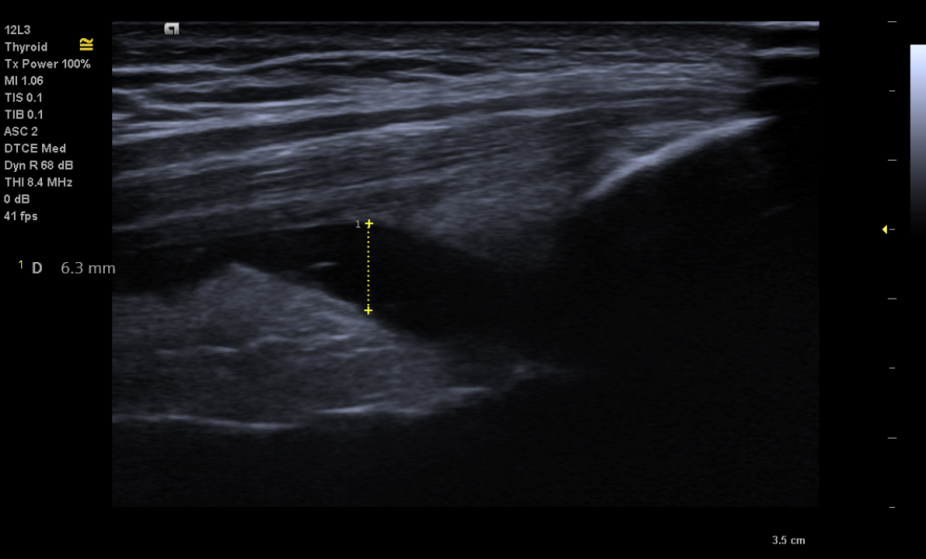

Hình ảnh viêm màng hoạt dịch và tăng sinh mạch máu màng hoạt dịch

Trên siêu âm, viêm màng hoạt dịch là hình ảnh: màng hoạt dịch tăng kích thước, dày lên, giảm âm, có thể có dịch trong khớp. Trên siêu âm Doppler năng lượng quan sát thấy màng hoạt dịch có các tín hiệu mạch. Tổn thương màng hoạt dịch trong VKDT, dẫn tới xuất hiện màng máu xâm lấn vào sụn khớp, huỷ hoại sụn khớp, đầu xương dưới sụn, hình thành hình ảnh khuyết xương (bào mòn xương) quan sát được trên siêu âm

Hình ảnh dịch khớp